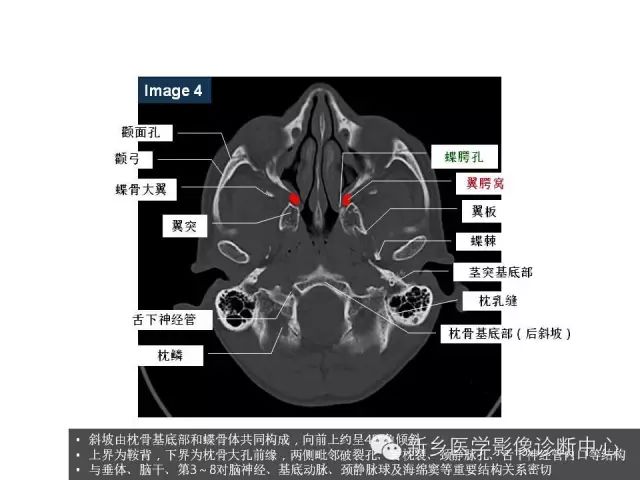

鼻咽部的详细解剖(含各个孔道)

来源:新乡医学影像诊断中心